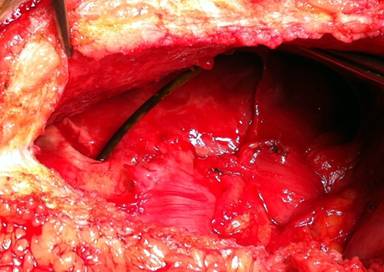

Because of the onset of peritonitis, the patient was subjected to exploratory laparotomy. Localized peritonitis with tenacious adhesions between intestinal loops and an interloop abscess were found intra-operatively. No enteric material was found. After careful debridement, the 7 cm long 6 Fr Nelaton stent which had been placed through the pancreaticojejunal anastomosis during PD, was found (Figure 2). The stent was free in the abdominal cavity and lying on a bowel loop where signs of sores were present (Figure 3). There was no evidence of bowel perforation, but intestinal loops covered with fibrin and suspect for impending perforation were resected. The whole small bowel was checked for other possible perforations, but no further injuries were detected. After abdominal cavity lavage, a drain tube was placed and the abdominal wall closed. Post-operative recovery was uneventful and the patient was discharged on the 6th post-operative day.

Figure 2. Intra-operative findings: perforated bowel and free stent. |

Figure 3. Decubitus sign of the stent on the small bowel mesentery after its removal. |

When perforation was detected, the laparotomic approach was preferred to laparoscopy since bowel adhesions consequent to the previous surgical procedure and induced by the long lasting bowel inflammation were expected. Even in the absence of an evident breaking point in the small bowel where perforation occurred, the most likely perforation site comprehensive of other injured and inflamed bowel segments was resected. The stent in this case was a 7cm long 6 Fr, tailored on Wirsung diameter, matching the depth of the remnant pancreatic duct. A larger and longer stent would have probably taken longer to pass through the entire bowel, but it was tailored to properly fit the Wirsung duct in order to minimize any risk of pancreatic leakage [30, 31]. There is a lack of evidence about the true rate of post-operative complications related to pancreatic stenting. We believe that in patients presenting with abdominal pain or peritonitis who previously underwent PD with stent-guided pancreaticojejunal anastomosis, the hypothesis of stent migration should at least be taken into consideration.